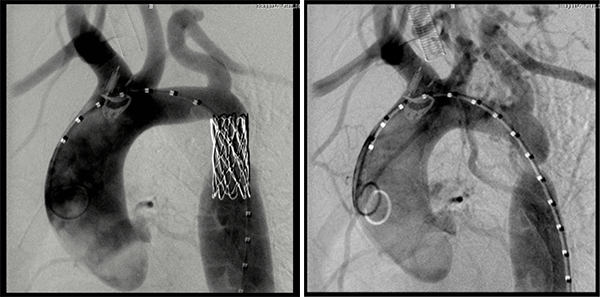

为了确保手术顺利,心脏外科二科李志强主任、成伟主治医师多次就手术事宜进行了详细讨论,对患儿入路血管直径、近端主动脉直径等主动脉各径线进行仔细测量,并做好了充分的术前准备工作。最终,经患儿右侧股动脉穿刺,将直径14毫米、长34毫米的支架成功植入主动脉,只留有5毫米的创口,手术获得圆满成功。此次使用的是CP支架,由特殊材料制成,如果日后患儿主动脉出现再狭窄,该支架可实现再扩张。

术后即刻,患儿主动脉近远端压差便消失了,上肢血压也恢复了正常,下肢血液灌注正常。术后12小时,患儿便可下地活动。患儿及家长对医护人员表示衷心感谢。